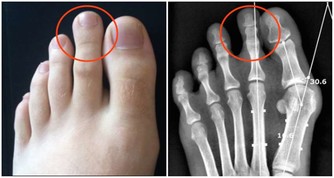

如果視力模糊,或有糖尿病足,或有糖尿病並發心髒病之類的情況就不適合強度運動,